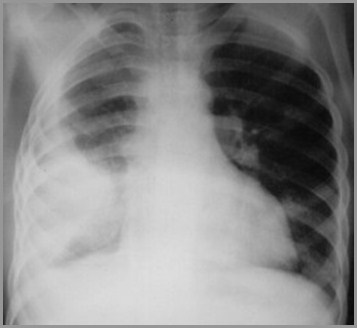

Opacified Hemithorax

If an effusion fills the entire hemithorax, itacts like a mass

There is displacement of the heart andtrachea away from the side of opacification

In atelectasis of an entire lung, the heartand trachea are pulled toward the side ofopacification

The righthemithorax isopaque

There is a shift ofthe heart andtrachea away fromthe side ofopacification

This ischaracteristic of apleural effusion

Large Right Pleural Effusion